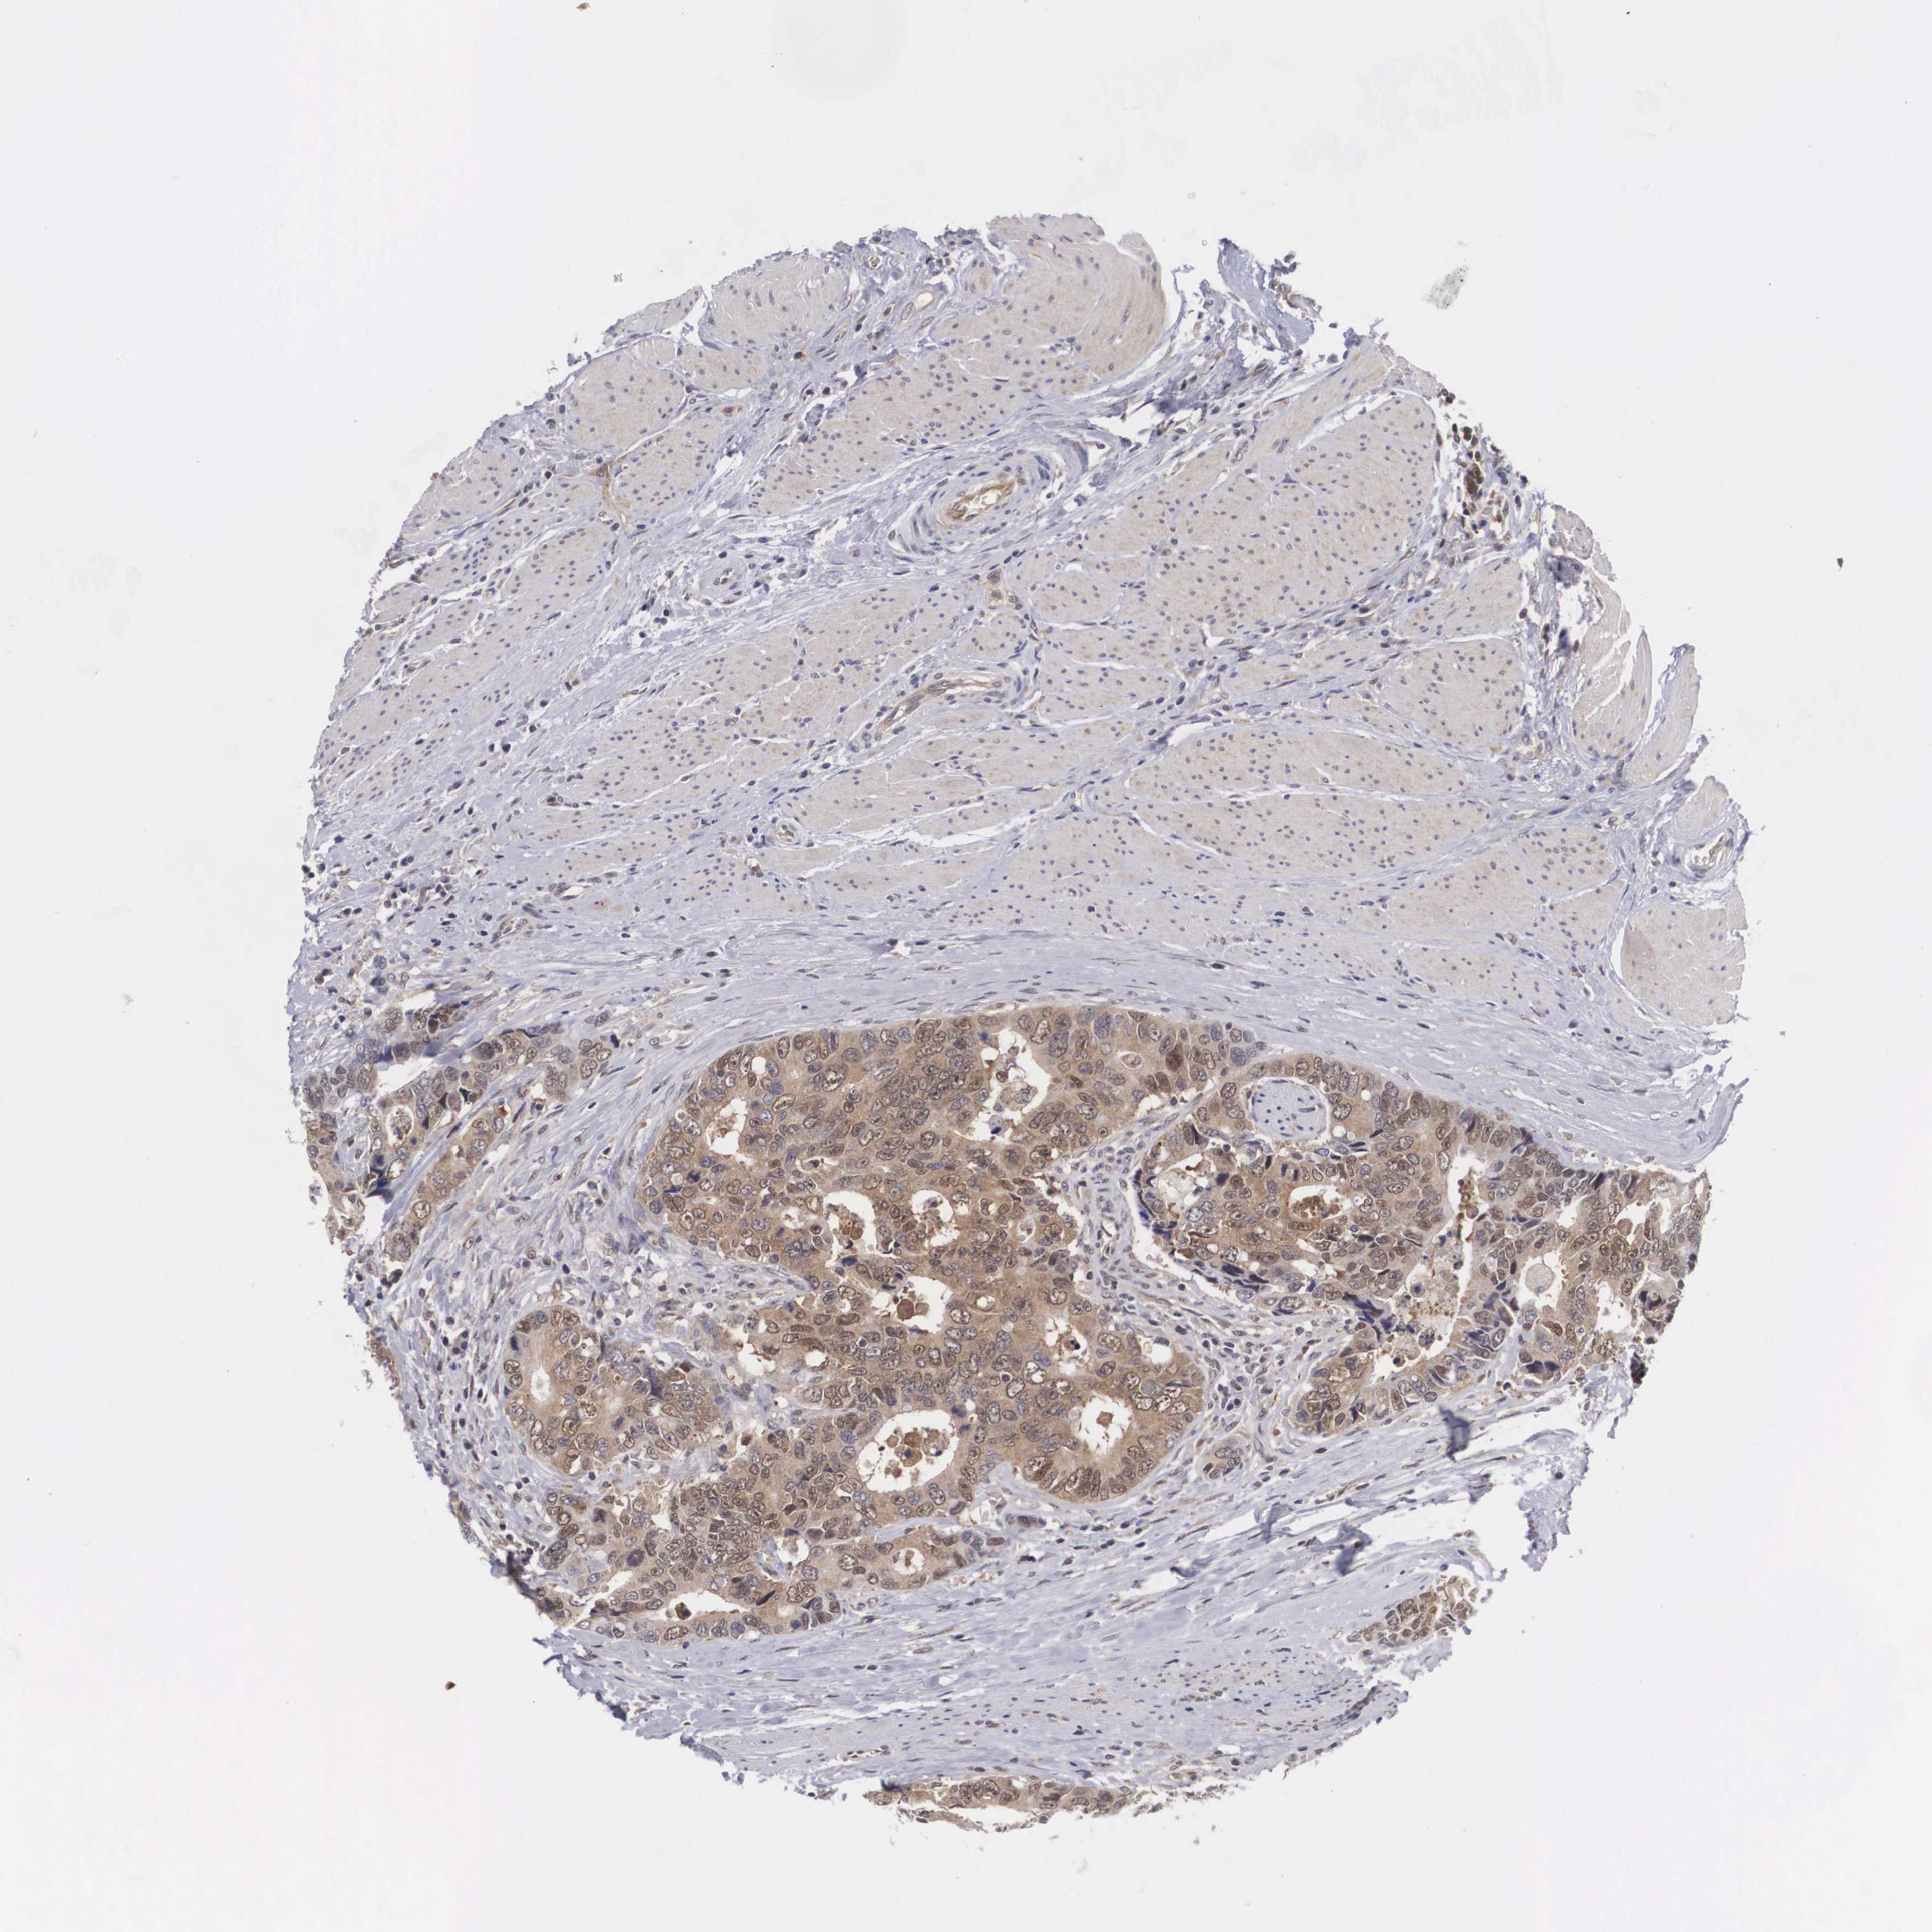

CANCER COLORECTAL CANCER Show tissue menu

Colorectal cancer

Human cancer